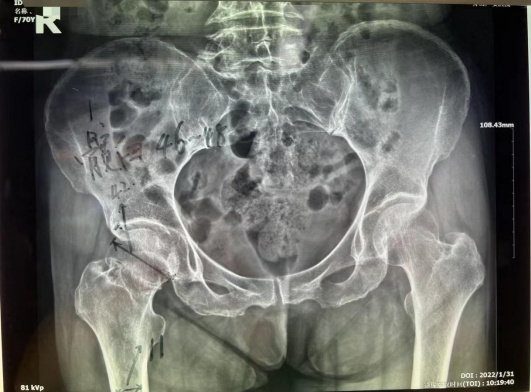

家住普陀的鄭阿姨今年70歲,大年初一在路上行走時(shí)不慎被電動(dòng)車撞倒,右髖部當(dāng)即動(dòng)彈不得。當(dāng)即被家人送來我院就診。門診拍片診斷為右股骨頸骨折,由于保守治療導(dǎo)致股骨頭壞死、骨折端不能生長的可能性極大。而且長期臥床也容易引發(fā)褥瘡、深靜脈血栓、肺部感染等并發(fā)癥。醫(yī)生建議其行全髖關(guān)節(jié)置換術(shù)。

患者為右股骨頸骨折